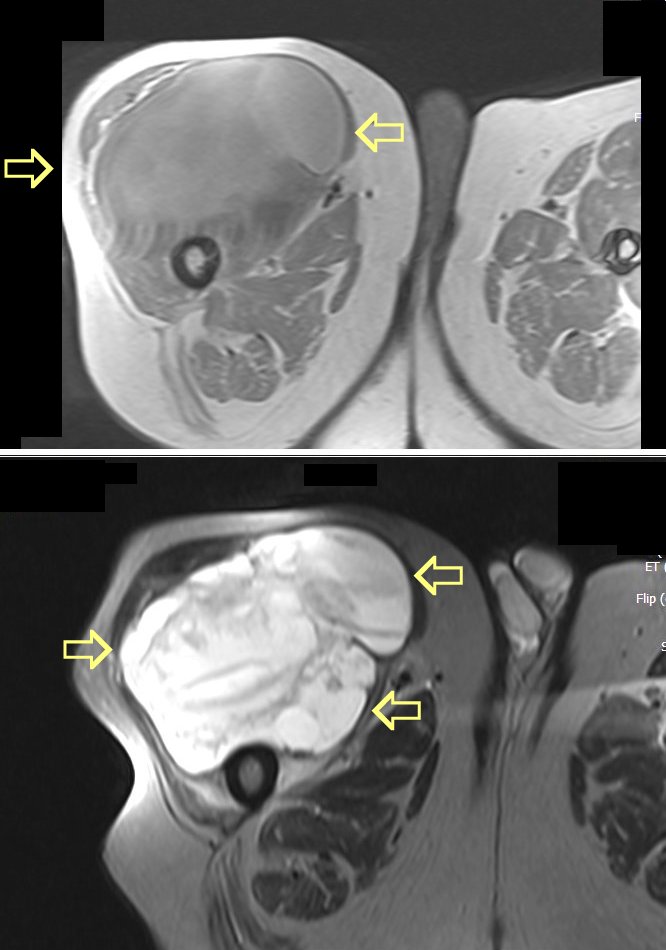

Patient with a large sarcoma in the right anterior thigh: CT here, MRI here and here, PET after neoadjuvant chemotherapy here and here

MRI Scan